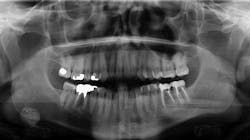

A healthy, 36-year-old male presented for a comprehensive exam. A panoramic radiograph revealed a well-defined, radiopaque lesion approximately 2x2 cm in size in the right submandibular region. The patient was unaware of its existence. The lesion was slightly palpable upon extraoral manipulation, but not necessarily tender.